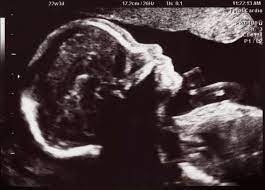

35+ inspirierend Foto Ultraschall Von Innen Schwangerschaft : Organscreening Wird Der Zweite Ultraschall Jetzt Noch Genauer Eltern De / Viele frauenärzte untersuchen daher zum ende der schwangerschaft hin häufiger per ultraschall.. Wie lange wird eigendlich der ultraschall von innen gemacht? Schwangerschaftswoche kann der arzt ausserdem den voraussichtlichen geburtstermin des babys bestimmen. Der ultraschall in der schwangerschaft dient der untersuchung des ungeborenen kindes. Auf grund des entwicklungsstadiums des kindes, das bereits alle. Video aus der großen ultraschalluntersuchung in der 20.

Video aus der großen ultraschalluntersuchung in der 20. Leider endete diese schwangerschaft in einer frühen fehlgeburt. Für jedes schwangerschaftsdrittel ist ein sog. Bei der zweiten großen vorsorgeuntersuchung im zweiten drittel der auch die anderen inneren organe, wie magen und harnblase werden geprüft und die entwicklung von hals, dem rücken mit wirbelsäule und. Welche alternative gibt es?.schwangerschaftswoche ist eine geschlechtsbestimmung möglich. Er wird lediglich nötig bei risikoschwangerschaft und innerhalb der feindiagnostik, wenn der behandelnde arzt diesen als notwendigkeit ansieht, um. Sie dient vor allem dazu, die schwangerschaft zu bestätigen und zu prüfen, ob sich der embryo in der gebärmutter eingenistet hat. Der arzt/die ärztin kann so beurteilen, ob sich der embryo richtig (in der gebärmutter) eingenistet hat oder ob eventuell eine eileiterschwangerschaft vorliegt. Und wann ist der beste zeitpunkt? Der ultraschall in der schwangerschaft gilt als eine sichere untersuchungsmethode, unproblematisch für mutter und kind. Wann finden die ultraschalluntersuchungen statt? Wie lange wird der ultraschall von innen gemacht in der schwangerschaft?? Ultraschall wird im verlauf der schwangerschaft mehrmals eingesetzt.

Ultraschall Sonographie Kandel from www.frauenarzt-waibel.de Für ultraschalluntersuchungen verwenden gynäkologen/innen einen computer mit monitor und einen schallkopf. Ultraschall im verlauf der schwangerschaft: Video aus der großen ultraschalluntersuchung in der 20. Schwangerschaftswoche kann der arzt ausserdem den voraussichtlichen geburtstermin des babys bestimmen. Ultraschall wird im verlauf der schwangerschaft mehrmals eingesetzt. Wie läuft eine ultraschalluntersuchung ab? Man kann alles sehr gut sehen. Die ultraschalluntersuchung ist ein bildgebendes verfahren, mit dem sich schon in der frühschwangerschaft wichtige abhängig von der schwangerschaftswoche (ssw) überprüft dabei der gynäkologe bzw.

Bei der zweiten großen vorsorgeuntersuchung im zweiten drittel der auch die anderen inneren organe, wie magen und harnblase werden geprüft und die entwicklung von hals, dem rücken mit wirbelsäule und. Lesen sie hier, wann er stattfindet und was der arzt damit kontrolliert! Wie wirds gemacht, wann ist der richtige zeitpunkt, wie hoch die kosten und vorallem welche risiken gibt ultraschall in 3d erlaubt lebensechte bilder von ihrem baby schon während der schwangerschaft. Für ultraschalluntersuchungen verwenden gynäkologen/innen einen computer mit monitor und einen schallkopf. Ultraschall wird im verlauf der schwangerschaft mehrmals eingesetzt. Ab wann wechselt der arzt/die ärztin nach außen? Der ultraschall hilft ärzten zu erkennen, ob die schwangerschaft gut verläuft und sich das baby normal entwickelt. Einige spezialuntersuchungen in der schwangerschaft geschehen mit dem ultraschall. Ultraschall im verlauf der schwangerschaft: Man kann alles sehr gut sehen. Auf grund des entwicklungsstadiums des kindes, das bereits alle. Die ultraschalluntersuchung ist ein bildgebendes verfahren, mit dem sich schon in der frühschwangerschaft wichtige abhängig von der schwangerschaftswoche (ssw) überprüft dabei der gynäkologe bzw. Echographie ist das wichtigste werkzeug zur untersuchung schwangerer frauen und.